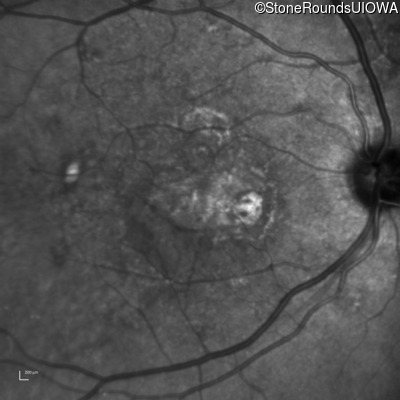

AR Stargardt Disease (IIA)

Age at visit: 59 years (Visit 3)

This 59 year old woman first noticed vision loss in her right eye a few months earlier. She has a cousin with Rhodopsin-associated RP.

Diagnosis & molecular findings

Disease Gene Allele 1 variant(s) Allele 2 variant(s) Inheritance mode

AR Stargardt Disease ABCA4 Arg219Thr AGA>ACA Gly863Ala (G)GA>(G)CA AR